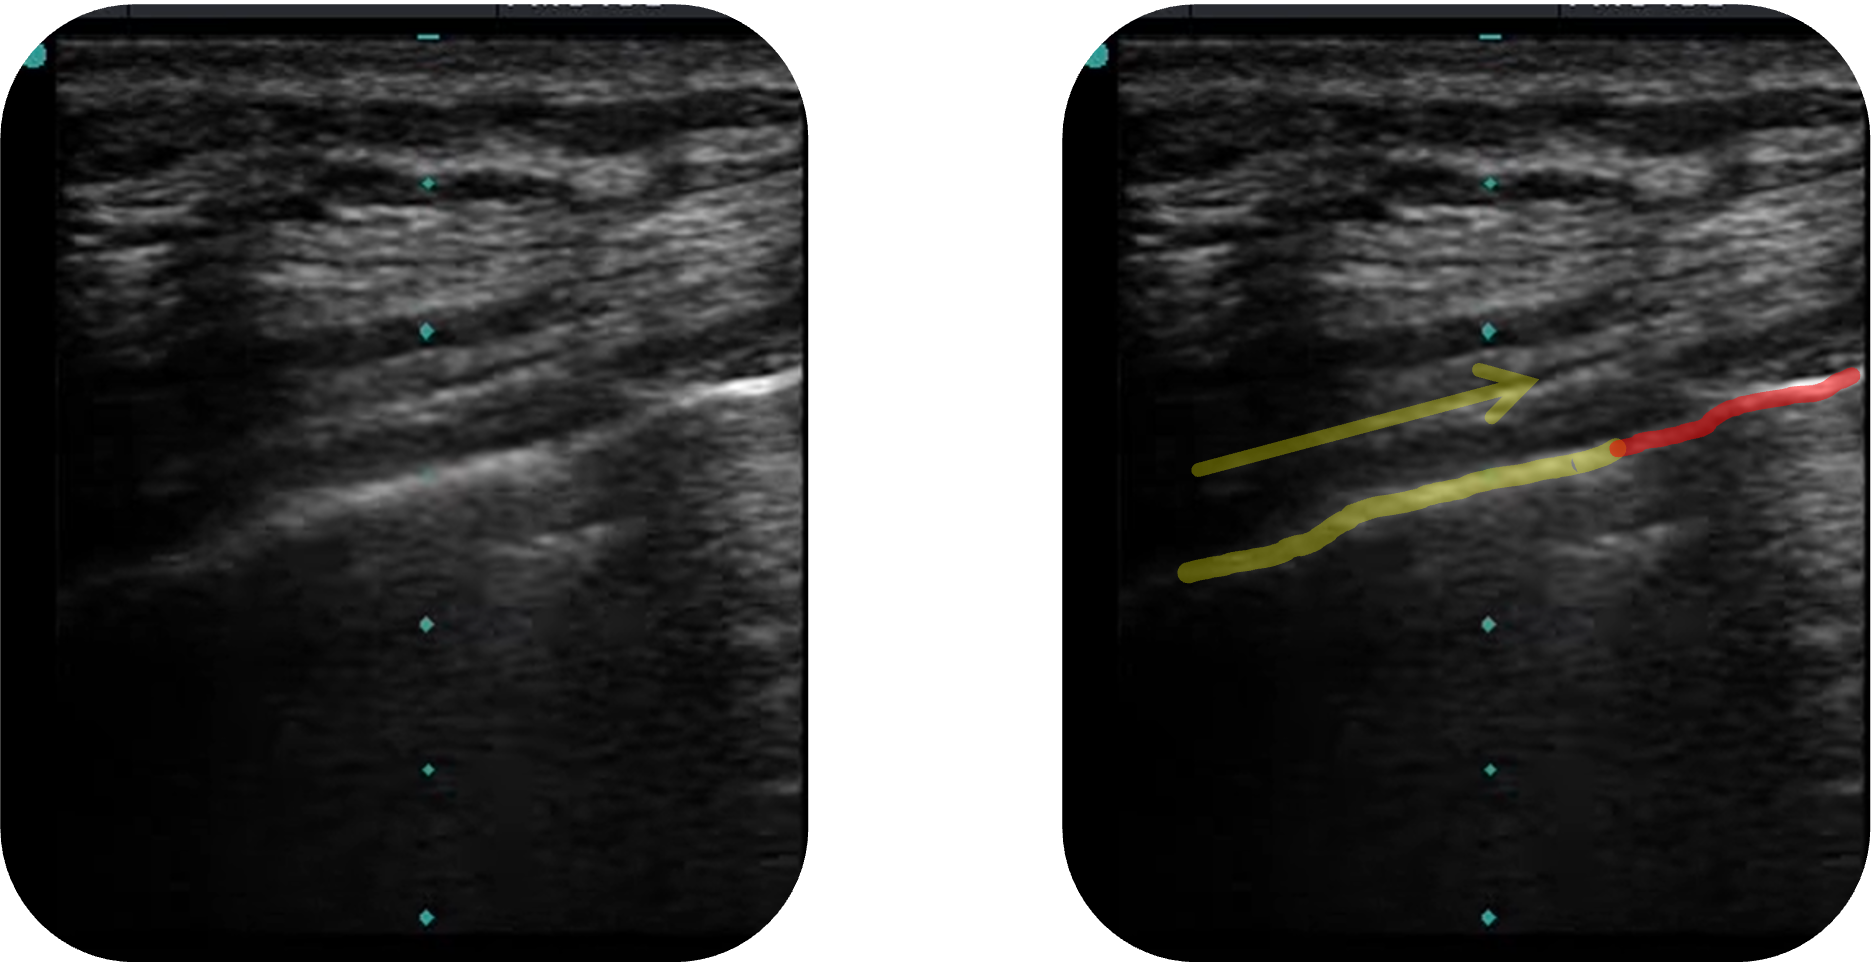

Lung-Point-Zeichen:

Das Lung-Point-Zeichen beschreibt den Übergangsbereich zwischen belüftetem und kollabiertem Lungengewebe.

Es entsteht, wenn sich der Luftsaum des Pneumothorax

Die Lage des Lung Points korreliert mit der Größe des Pneumothorax

Obwohl das Lung-Point-Zeichen in der Praxis nicht immer leicht zu finden ist, gilt es bei Nachweis als pathognomonisch für einen Pneumothorax

Portable-bedside-ultrasound-the-visual-stethoscope-of-the-21st-century-1757-7241-20-18-S4.ogv, Gillman L, Kirkpatrick A, CC BY 2.0, https://creativecommons.org/licenses/by/2.0, via Wikimedia Commons, Teilausschnitt aus dem Originalvideo. Es wurden die Markierungen ergänzt.

Der gelb markierte Teil der Pleura bewegt sich in Pfeilrichtung vorwärts, der rote Bereich bleibt aufgrund des Pneumothorax